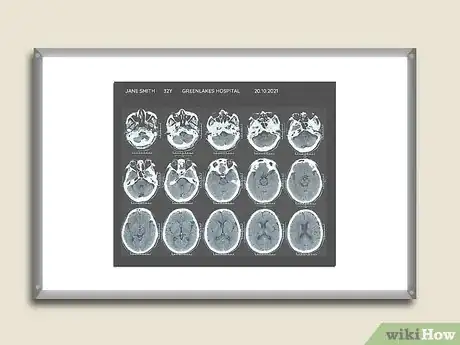

A computed tomography (CT) scan can create cross-sectional images of any part of your body using special X-rays and a computer.[1] This type of radiology study is an important part of diagnosing medical diseases like strokes, cancers, and infections in the abdomen like appendicitis. You can learn to read a CT scan if you understand the normal anatomy and what the shades of white, grey, and black on the films mean.

Read the information on the CT scan. Check to see what is printed on the films to determine they are yours and what part of the body is represented in the films.

• You should see your name and other identifying information like your birthdate. The name of the hospital or medical facility where the films were taken and the date the study was performed should be printed on each film. You do not want to look at someone else’s films and become upset if you see an abnormality.

• Your expectations about what you will see are determined by what part of your body was studied. The CT of your brain will be compact with your brain encased inside the thin bone of your skull. The CT of your leg or arm will be compact but it will have length; the scan will have images of your bones and the surrounding soft tissue (muscle and fat). The CT of your abdomen will be large and very complex because you will be seeing things like your small intestines curled up like a snake right next to your kidneys, liver, spleen, etc.